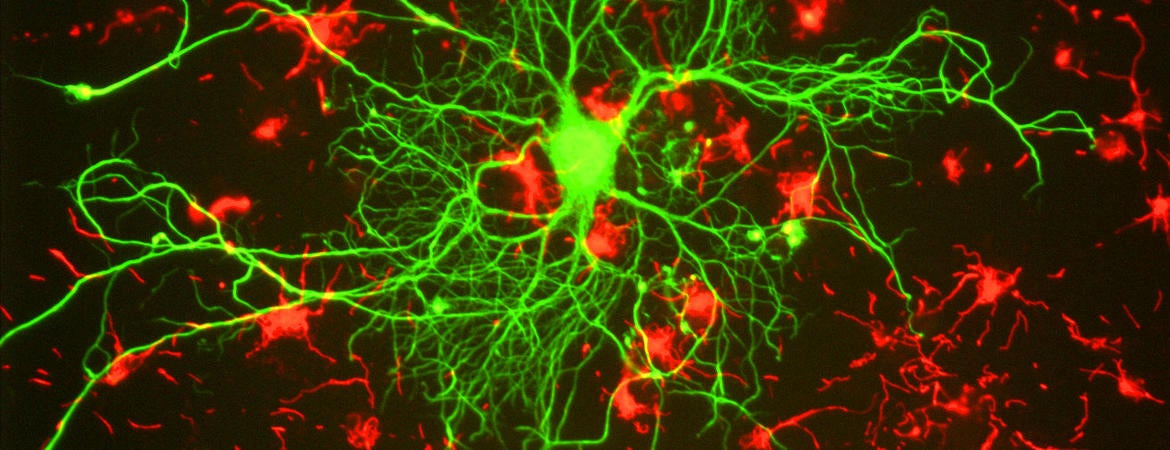

Spinal cord from animal model of MS